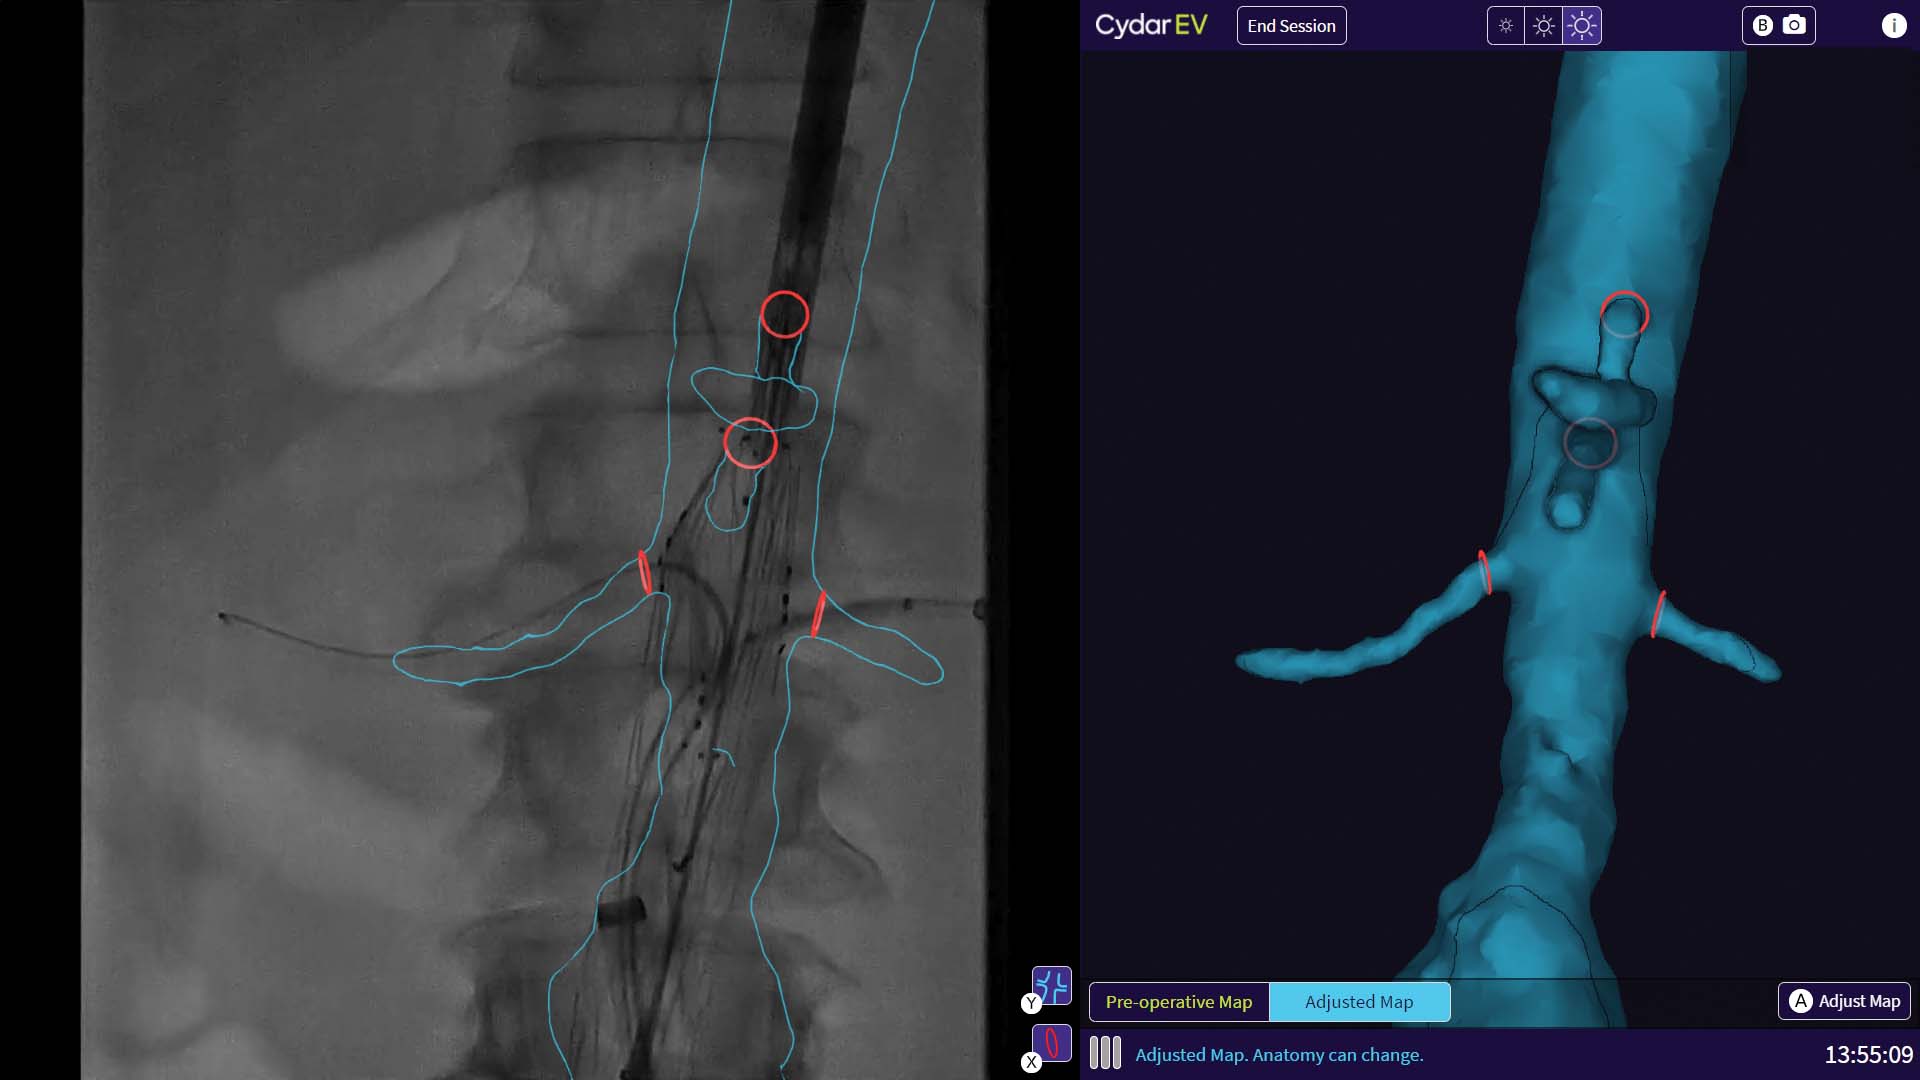

Cydar EV Maps assists in the planning, real-time guidance, and post procedure review of endovascular surgery. It brings cloud-based AI and computer vision to mobile surgery, enabling reductions in radiation exposure, fluoroscopy time, and procedure time together with improved ease of use [1,2]. It enables surgeons to create a detailed patient-specific 3D map of the target vasculature to help plan surgery, and then uses these maps to augment intraoperative live image-guidance, updating the maps in real time to account for deformations during surgery, such as guidewires and instruments deforming the patient’s blood vessels. Cydar EV also facilitates post procedure outcome analysis. The combined result of this integration of procedure planning, guidance and review is that surgeons can work more accurately and efficiently – enabling an approximate 50% reduction in radiation exposure [1], a significant reduction in fluoroscopy time and a reduction of procedure times by more than 20% [2], while helping achieve better outcomes for patients.

Cydar Limited specializes in medical computer vision, machine learning and cloud high-performance computing. Cydar EV is a cloud-based software platform that generates patient specific 3D Maps of soft tissue vasculature to support more effective image guided, minimally invasive endovascular surgery. The system comprises pre-operative procedure planning functionality and real time, AI enabled 3D intra-operative imaging and procedure guidance, with procedure video capture and post procedure review functions.

Cydar EV Maps harnesses the latest in cloud GPU computing, computer vision and machine learning technology to advance surgical visualization and decision-making in theatre and across the surgical pathway. Cydar’s Surgical Intelligence system is learning from every case to develop a deeper understanding of surgery.